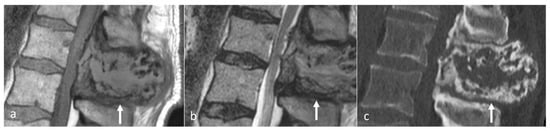

The typical imaging appearance is a well-circumscribed lytic lesion. They can occasionally be expansile and also sclerotic (Figure 6a–c). On MRI, the lesions typically appear as a T1 and T2 hypointense mass, which shows high signal on T2 STIR or T2 fat-saturated images. The lesions enhance after contrast administration [27].

Figure 6.

Sagittal T1 (a), T2 (b) and CT (c) images of a sclerotic myelomatous deposit involving a thoracic spinous process (white arrows). While myeloma typically tends to present as lytic lesions, occasionally they can be expansile and sclerotic as seen here.